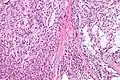

Low mag. High mag.

High mag.